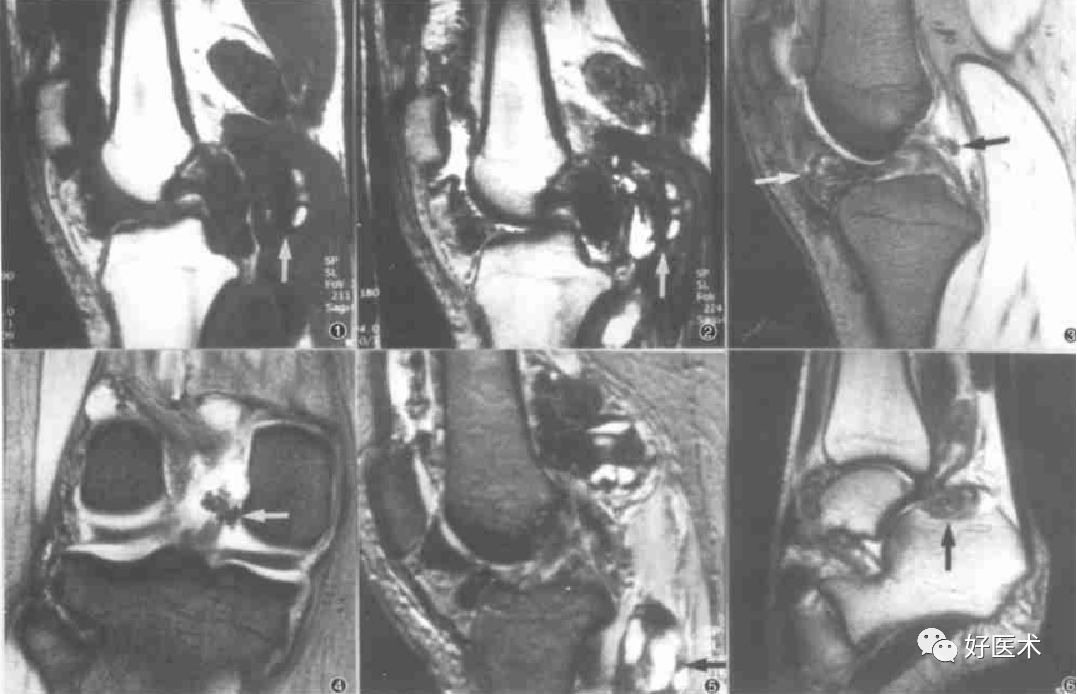

MRI表现

MRI对膝关节PVS具有定性诊断意义,它可以清楚显示病变的范围、关节软骨及骨质破坏的程度,其特征性表现为T1、T2加权像时低密度信号区。故MRI已成为X线片检查后首选的影像学检查方法。术前MRI检查不仅有助于明确关节内、外病变程度和范围,同时,术后MRI检查也是检查病变复发与否的最敏感手段。

髌下脂肪囊及关节腔滑膜呈绒毛、结节样隆起,并可见形态不规则T1、T2双低信号含铁血黄素沉着,关节积液

滑膜弥漫增厚,髌上囊、髌下脂肪囊及关节腔滑膜呈绒毛、结节样隆起,并可见形态不规则T1、T2双低信号含铁血黄素沉着,关节积液